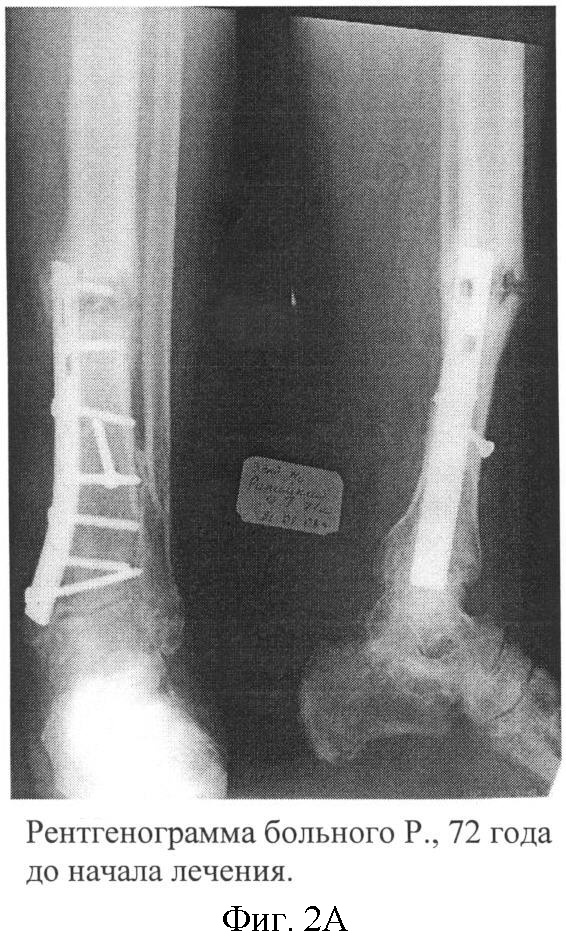

Больной Р., 72 года, поступил в хирургическом отделении МУЗГКБ 2 с диагнозом: «Хронический посттравматический остеомиелит левой большеберцовой кости в средней трети, свищевая форма; патологический перелом с признаками ложного сустава в средней трети левой большеберцовой кости, в условиях ОМС (пластина с шурупами)». Травма 2.5 года назад – закрытый перелом костей левой голени в нижней трети. После накостного остеосинтеза развился остеомиелит. Проводимые лечебные мероприятия привели к консолидации перелома в нижней трети, но у больного сохранялся свищ с гнойным отделяемым и остеомиелитический процесс перешел в среднюю треть большеберцовой кости, где на уровне проксимального шурупа произошел патологический перелом (фиг.2А). Больной передвигался с помощью костылей без опоры на больную конечность. 24.02.08 г. выполнена операция – иссечение свища, удаление металлоконструкции, некрсеквестрэктомия, дренирование остеомиелитического очага. Иммобилизация гипсовой повязкой. Купировав острый воспалительный процесс, выполнены трансплантации МНК и МСК по описанной схеме. Отмечено заживление послеоперационной раны первичным натяжением, без признаков рецидива воспалительного процесса за период наблюдения. Через 3 месяца после имплантации: клинически перелом консолидировал, гипсовая повязка заменена на съемную гильзу. На контрольной рентгенограмме отмечается выраженная костная мозоль в области перелома средней трети большеберцовой кости. Периостальная реакция не отмечается (фиг.2Б). Больной ходит, используя трость с опорой на пораженную конечность. Данная картина сохраняется через 6 месяцев.